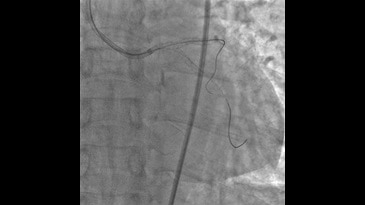

Моторизованное движение по 3-м осям делает даже наиболее сложные проекции легкодоступными. L-штатив вращается вокруг вертикальной оси на +100° (+/- 95° моторизованно). Комбинация движений С-шатива и L-штатива обеспечивает ангуляцию краниально и каудально от -50° до +45°. Изгиб С-штатива обеспечивает вращение в диапазоне -117°/+105° RАО/LАО. Глубина изгиба С-штатива — 107 см (42″) при позиции L-штатива на 0° обеспечивает поперечное покрытие тела большинства пациентов.